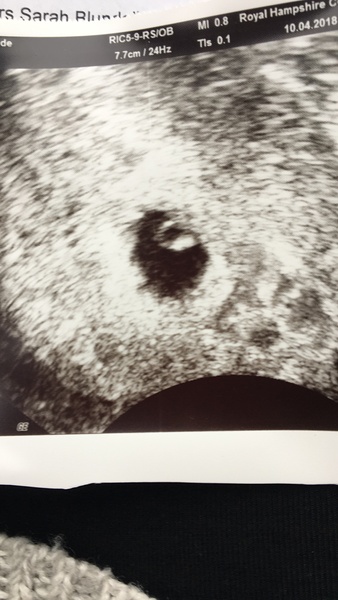

natashaarr · 10/04/2018 11:59

@yukka thank you!! The scan went amazing, we saw a heart beat! They don’t want to see me until 12 weeks so just over 5 weeks without a scan worries me but for now we are very very happy ☺️ You can’t see much but here’s the photo xxx